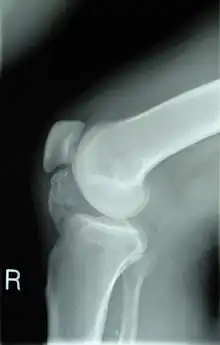

Lateral radiograph of the knee demonstrating ossification in the peritendinous tissues in a patient with osteochondroma.

• X-rays are the first tests performed that characterize a lesion. They show a clear picture of dense structures of bones, and will also indicate bone growth pertaining to osteochondroma.[5][11]